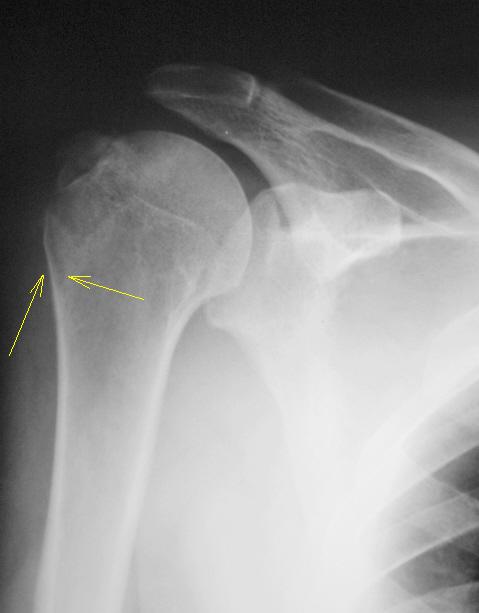

Травма. пациент направлен хирургом в рентгеновский кабинет для рентгенографии плечевого сустава. Были произведены рентгенограммы в двух проекциях. Могу представить, увы, только изображение в прямой проекции.

Насчет линейной тени (две медиальные стрелки) - думаю, не перелом это, закрытая зона роста.

Однозначно, линия, указанная стрелками, это бывшая ростковая зона.

Мое мнение, что анатомическая шейка плечевой кости абсолютно интактная! Пациент достаточно молод.